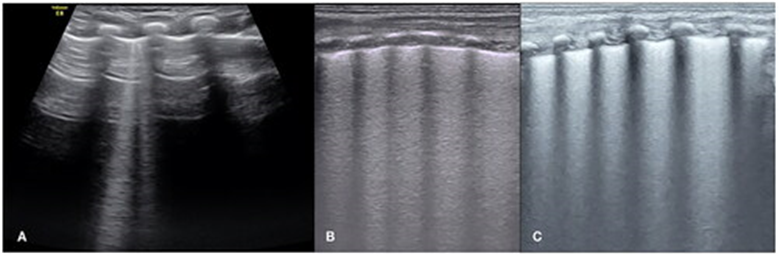

Ультразвуковое исследование легких отличается от исследования других органов тем, что оно сочетает в себе интерпретацию реальных анатомических изображений с интерпретацией артефактов, генерируемых ультразвуковым лучом на границе раздела «воздух/жидкость» [69]. В нормальной воздушной легочной ткани основная часть ультразвукового сигнала отражается от воздуха, содержащегося в легких. Поэтому визуализировать неизменённую легочную ткань не представляется возможным. Однако при морфологических нарушениях, а следовательно, при изменении физических свойств легочной ткани, формируются акустические эффекты, которые можно выявить при проведении УЗИ [70].

А-линии представляет собой отражение от плевральной линии вглубь изображения в результате эффекта реверберации и выглядит как горизонтальные гиперэхогенные повторяющиеся линии, расположенные через одинаковые промежутки. Данный артефакт является признаком нормального или избыточного содержания воздуха в альвеолярном пространстве.

В-линии – гиперэхогенный артефакт “хвоста кометы”, вызванный отражением ультразвука от границы газ-жидкость. Возникают от плевры и проходят вертикально через весь экран. В-линии - артефакт, который указывает на увеличение плотности исследуемого участка легкого, снижение его воздушности. В-линии появляются в результате попадания УЗ-луча на границу между утолщенной междольковой перегородкой и воздушными альвеолами, то есть на границу сред с сильно отличающимся акустическим импедансом, в результате чего возникают множественные вертикальные реверберации. Наличие данного УЗ-феномена не является специфичным признаком, а свидетельствует об интерстициальных изменениях (интерстициальный синдром). Субстратом данного УЗ явления считается появление избыточной жидкости в интерстициальном пространстве легочной паренхимы, либо уплотнение междольковых перегородок [71]. При прогрессировании интерстициальных изменений количество В-линий увеличивается, они сливаются друг с другом вплоть до появления единого эхопозитивного изображения. Данное явление получило название «белое легкое» (white lung) (при продольном сканировании перпендикулярно ребрам – признак водопада (waterfall sign)) и является отражением альвеолярно-интерстициального синдрома.

Одним из наиболее часто встречающихся ультразвуковых признаков при ТТН является «двойная точка лёгкого» (DLP). «Двойная точка лёгкого» (DLP) – четкая граница эхогенности между нижними легочными полями (с наличием гиперэхогенной тонкой плевральной линии, наличием компактных B-линий) и верхними легочными полями (с наличием, как правило, нормальной эхогенности [74] (диапазон чувствительности данного признака сильно различается (45,6 – 100%); диапазон специфичности 94,8 – 100%).

«Двойная точка лёгкого», наличие В-линий и «белое легкое» являются основными ультразвуковыми характеристиками ТТН [72]. Однако, ультразвуковая картина ТТН может быть вариабельна, например, частичное или полное исчезновение «А-линий» (гиперэхогенные горизонтальные линии на равных промежутках от плевральной линии и друг от друга, свидетельствующие о нормальной аэрации лёгкого) в начальной стадии заболевания, появление 3 и более В-линий, и «белое легкое» (сливающиеся В-линии) при тяжелых проявлениях [67]. ТТН можно исключить при наличии легочных консолидаций и воздушных бронхограмм [67],[73].

Ультразвуковые критерии ТТН: комбинация признаков «двойная точка лёгкого» (double lung point, DLP) и B-линий [67].

Комбинация ультразвуковых признаков («двойной точки лёгкого» (DLP) и наличия B-линий) является более точным диагностическим критерием по сравнению с оценкой только DLP (объединенная чувствительность – 98%; объединенная специфичность – 99%).